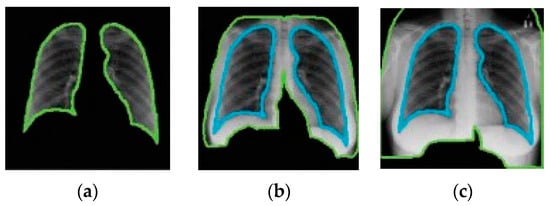

4.2. Segmentation

Like data augmentation, segmentation is a pre-processing step applied to CXR images [60]. Segmentation is typically performed to locate objects (e.g., lungs) and boundaries (e.g., lung boundaries) in images (e.g., CXR images) [61]. It enables the extraction of desired regions of interest from CXR images. Manual segmentation is tedious and time-consuming and relies on the expertise of radiologists. DL-based segmentation models have been used to obtain the lung region in CXR images. Narayanan et al. [62] have made use of CXR image segmentation as a pre-processing step. They did this using a DL-based segmentation model called U-Net [63]. Through segmentation, they were able to find out that the shape of the lung is key to differentiating between viral and bacterial pneumonia. The performance of the classification model improved as a result of incorporating segmentation in the process.

A number of DL-based segmentation models exist such as fully convolutional networks (FCNs) [64], U-Net [63], and V-Net [65]. U-Net is the most popular architecture [60]. The following are some of the studies that have exploited segmentation in CXR-based pneumonia detection: [66,67,68,69,70,71].